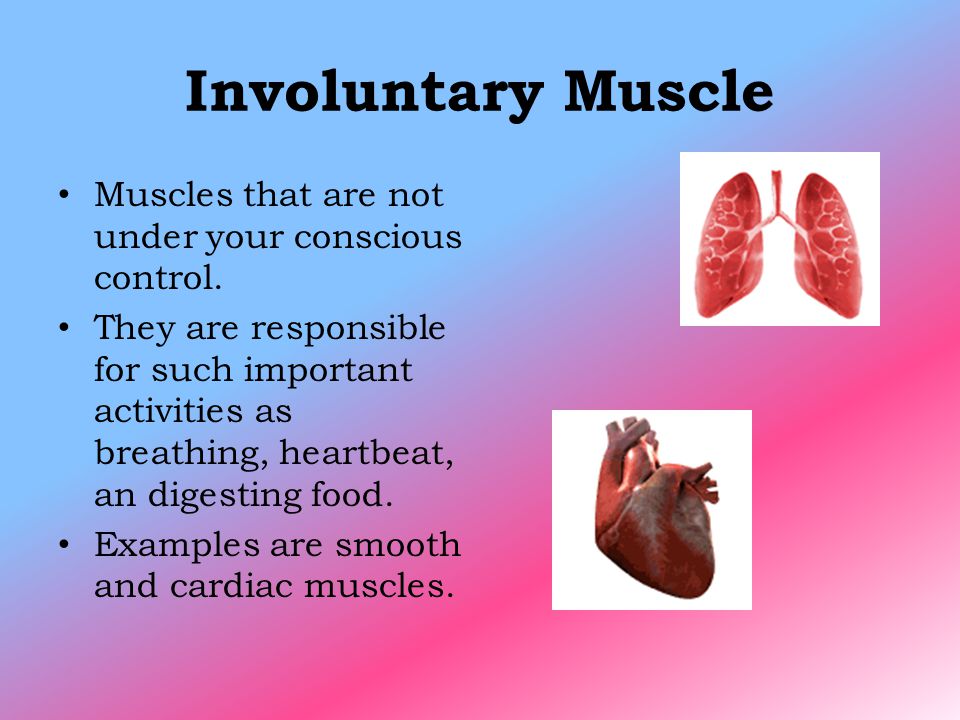

Involuntary muscles move on their own without us being aware that they are moving e.g. the heart muscles, inter coastal muscles.

Involuntary muscles move on their own without us being aware that they are moving e.g. the heart muscles, inter coastal muscles.